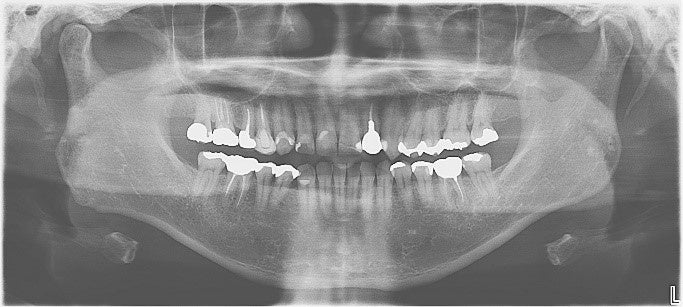

■パノラマエックス線撮影

口、顎全体を1枚の写真に写すエックス線撮影では、むし歯や歯周病、のう胞、腫瘍、唾石、骨折など歯と顎骨の中の病気や、上顎洞(副鼻腔)の炎症有無などを診ることができます。